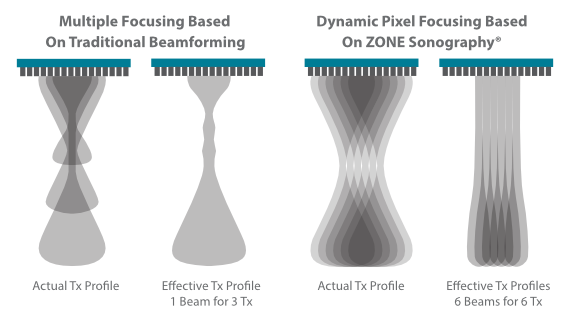

Pemfokusan Piksel Dinamis